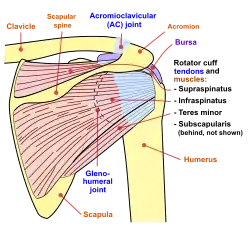

Diagram of the human shoulder joint, front view Diagram of the human shoulder joint, back view

Diagram of the human shoulder joint, back view Muscles of the neck. Anterior view.